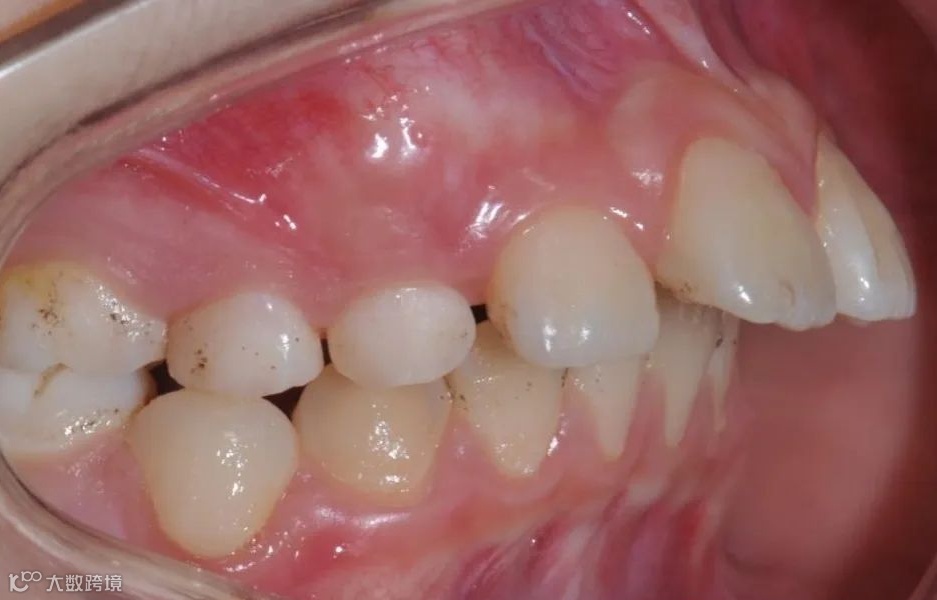

治疗前右侧咬𬌗相

治疗前正面向咬𬌗相

治疗前左侧咬𬌗相